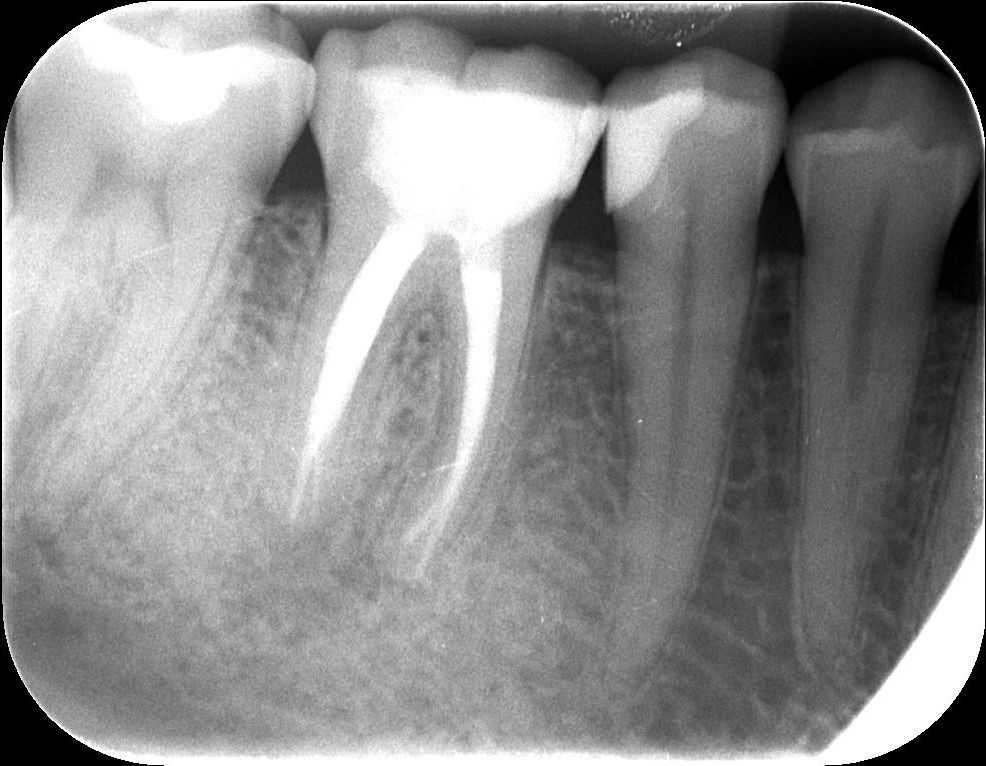

Az alábbi felvételen látható a kész gyökértömés első szakasza, amikor a gyökértömés alsó harmadát készítjük el meleg guttapercha-technikával. A kiindulási röntgenfelvétellel összehasonlítva látható, hogy a gyökértömő anyaggal szépen sikerült elérni a gyökércsúcsok végéig.

mikroszkópos gyökérkezelés 3. kép